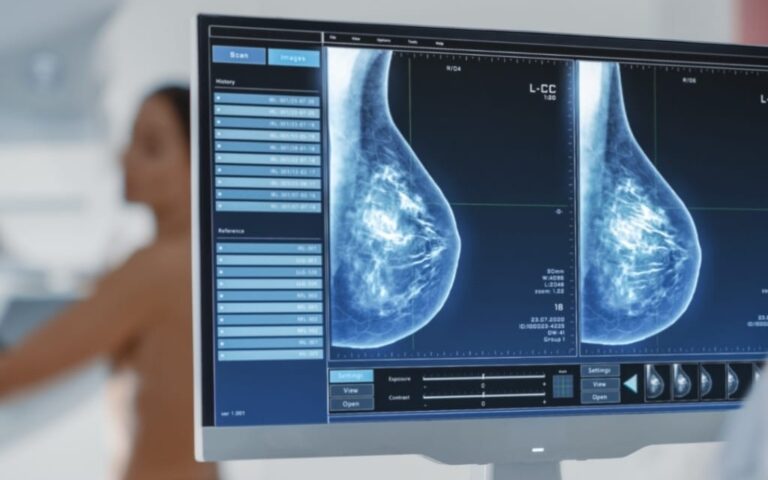

C’est une radiographie des seins, qui utilise donc des rayons X.

Elle comporte au minimum 2 clichés de chaque sein (de face et oblique) et peut être complétée par un cliché de profil ou des clichés centrés sur une région particulière du sein.

Cet examen permet d’obtenir certaines informations sur les seins qu’aucun autre examen ne peut fournir, les autres examens (tels l’échographie, l’IRM) apportant éventuellement des informations complémentaires si les résultats de la mammographie le justifient.

L’interprétation des clichés sera effectuée par le radiologue qui vous remettra les clichés accompagnés d’un compte-rendu.